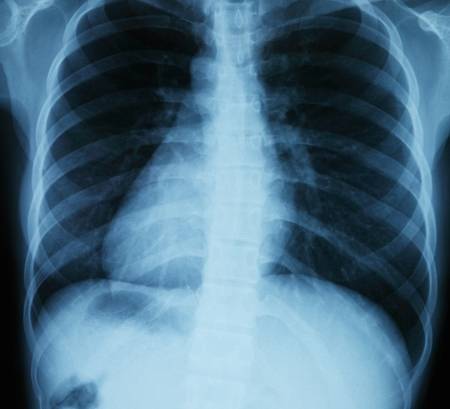

◆ 교정이 필요한 척추질환

척추 질환과 척추 변형 등에 따라 치료 방법이 개인마다 달라 질 수 있기 때문에 환자의 상태를 정확하게 파악하여 환자와 함께 치료 계획을 세우게 된다.척추교정은 경추, 흉추, 요추, 골반 등 전 척추의 구조적 이상을 진단하고 이를 정상적인 구조로 회복시키는 것으로 자세교정운동요법, 교정요법 등 상태에 따라 복합적인 치료를 하게 된다.

틀어진 척추는 반복적이고 만성적인 통증을 유발하고 신체 내부 장기의 생리적 기능까지 망가뜨릴 수 있으므로 정확한 진단에 따른 척추교정이 필수적이다.